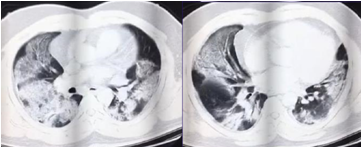

3.胸部影像學(xué)表現(xiàn)

早期呈現(xiàn)多發(fā)小斑片影及間質(zhì)改變,以肺外帶明顯。進(jìn)而發(fā)展為雙肺多發(fā)磨玻璃影、浸潤影,嚴(yán)重者可出現(xiàn)肺實變,胸腔積液少見。

重癥患者,雙肺呈彌漫性病變,以實變影為主,合并GGO